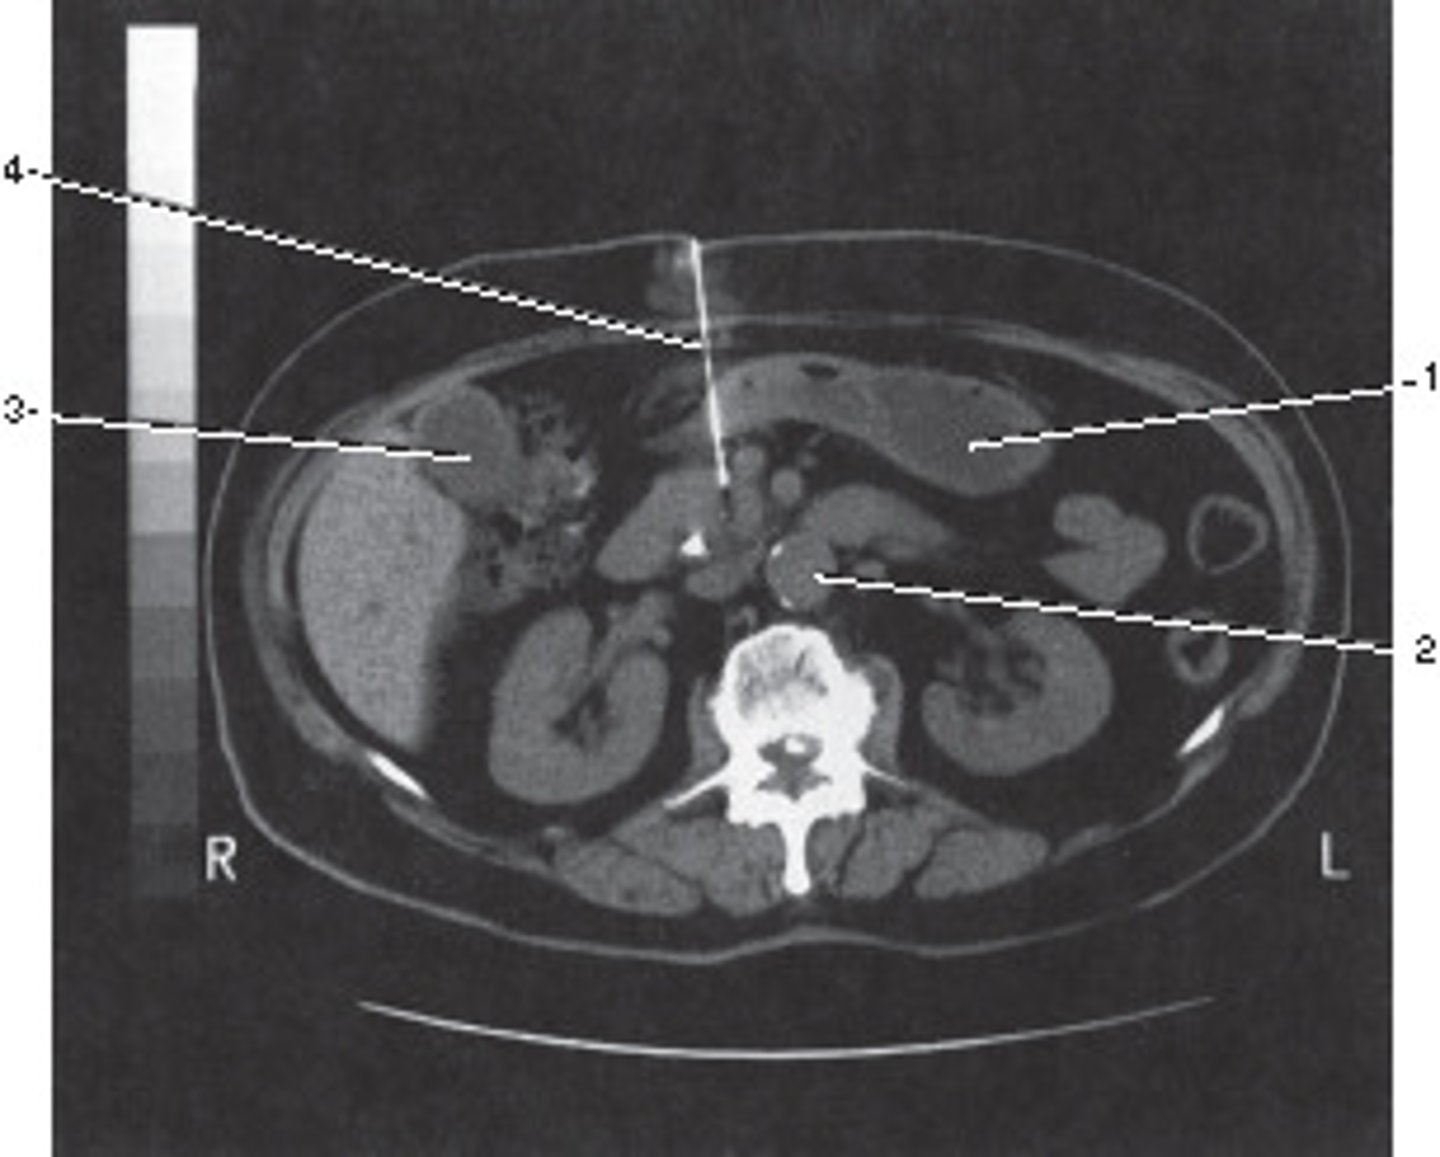

Corticomedullary;

30-40 seconds after injection,

the corticomedullary phase demonstrates optimal enhancement of the renal cortex with maximum differentiation from the renal medulla

This image of the abdomen was most likely acquired in which in which renal enhancement phase?

<p>This image of the abdomen was most likely acquired in which in which renal enhancement phase?</p>

Portal Vein

Number 1 corresponds to which of the following?

<p>Number 1 corresponds to which of the following?</p>

Renal Cortex

Psoas Major Muscle

Number 2 corresponds to which of the following?

<p>Number 2 corresponds to which of the following?</p>